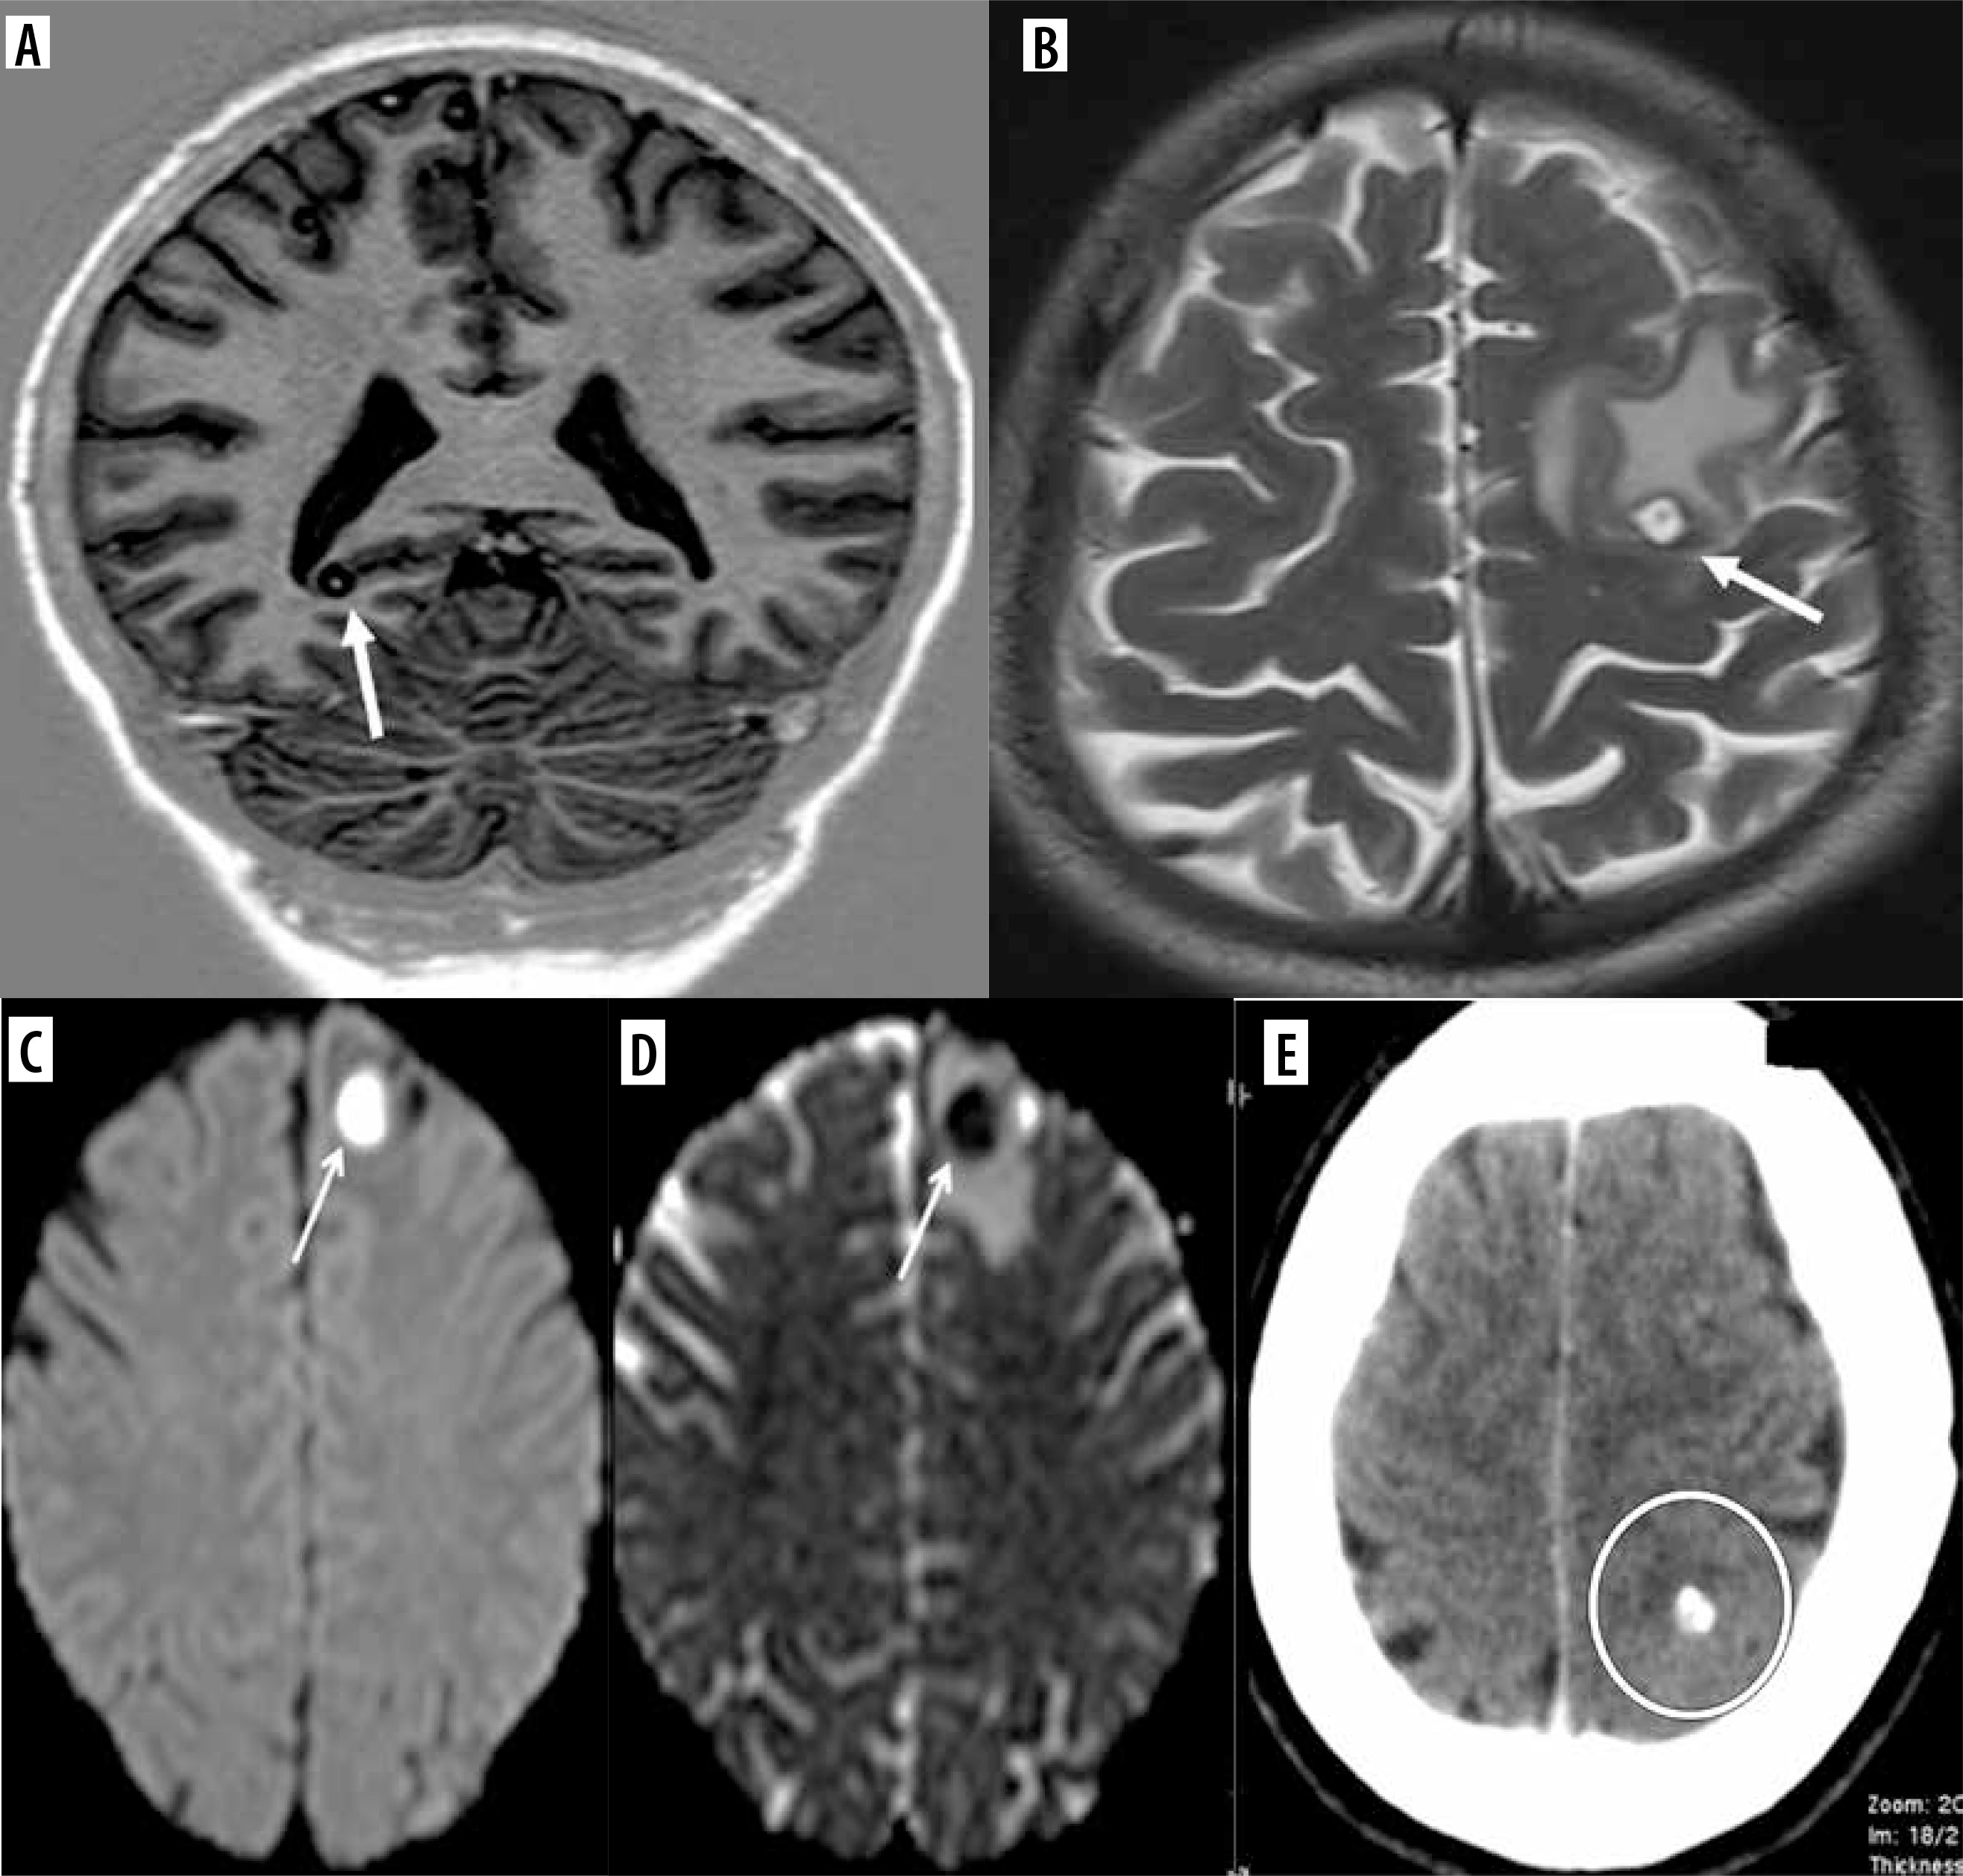

Figure 3

Intracranial neurocysticercosis lesions in our patients. A) Post-contrast fat saturated T1 coronal image shows a solitary ring enhancing lesion (arrow) in the right occipital cortex minimal perilesional edema. B) T2 coronal image shows few conglomerated lesions (arrow) in the occipital lobe with moderate perilesional edema. C) Post-contrast fat-saturated T1 axial image shows multiple small ring enhancing lesions in bilateral cerebral hemispheres (arrow). D) Axial CT shows a calcified lesion (circle)

Different stages of the disease were seen in the same patient. Stages were defined accordingly. Stage 1 is vesicular, stage 2 is colloidal, stage 3 is granular nodular and the last stage is nodular calcified stage. Stage 1 often occurred alongside other stages of the disease in the same patient. Most patients had stage 3 disease, comprising 39%, followed by 29% with a combination of stage 2 and stage 3 disease of NCC. Only 14 patients exhibited stage 4 NCC, a few of whom had a history of seizures and headaches, while most were incidentally detected (Figures 4 and 5).

Figure 5

Stages of neurocysticercosis (NCC). A) Coronal T1 FLAIR image shows a well-defined cystic lesion with iso or hyperintense scolex in the background of hypointensity (arrow) in the right occipital cortex, representing the vesicular stage. Note that there is no perilesional edema. B) Axial T2 image shows a round hyperintense cystic lesion with hypointense rim and a scolex, associated with perilesional edema representing the colloidal stage (arrow). C, D) Stage 3 of NCC showing diffusion restriction of the cyst with perilesional edema suggesting a degenerating cyst (arrows). E) Axial CT showing calcified cyst depicting stage 4 disease (circle)